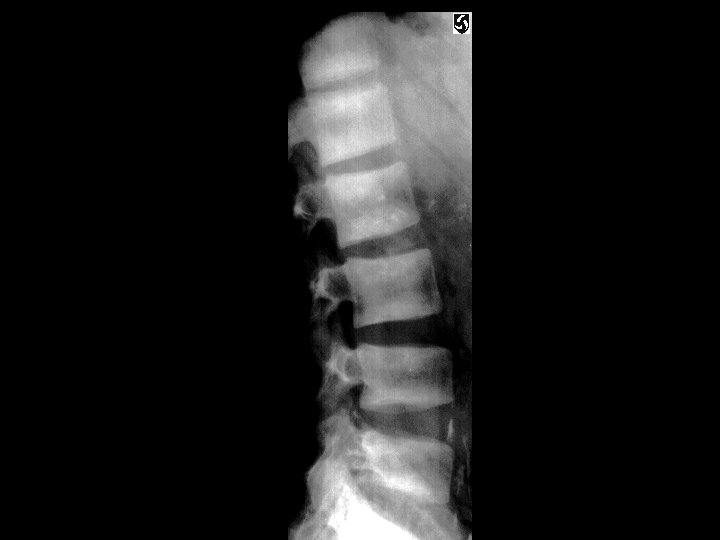

Renal osteodystrophy • Findings: – Osteopenia – Prominent trabecular pattern – “rugger jersey” spine • ddx: – NONE! – This is an Aunt Minnie!